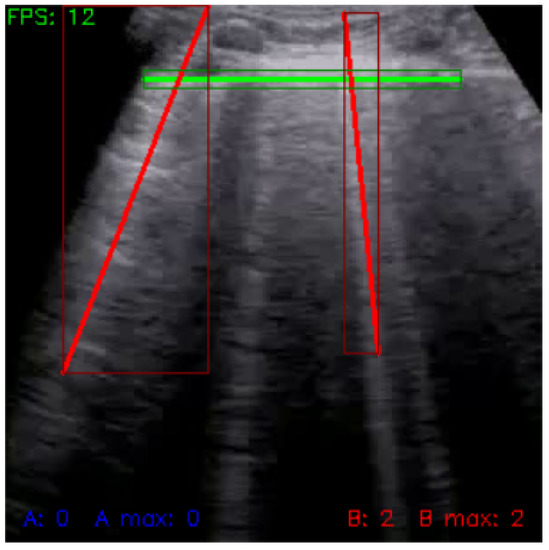

In the last step of line detection, we transformed the detected lines into vectors (step e in Figure 3). Horizontal A-lines were transformed into a constant function (Equation (1)), vertical B-lines were transformed into a linear function (Equation (2)), while tangent a and constant y 0 were determined using least square approximation. Each detected line was then saved as two points (starting and ending) with x and y coordinates on the image. Figure 7 shows a sample of the final output of line detection.

A key indicator of the analytical approach’s success is its ability to process videos in real-time. During our experiments, we achieved a frequency of at least 12 FPS on various commercially available mid-range computers, pointing at the accessibility of our solution in everyday use with no dedicated hardware required.

Figure 7. Frame with detected lines (green: pleura, red: B-lines).